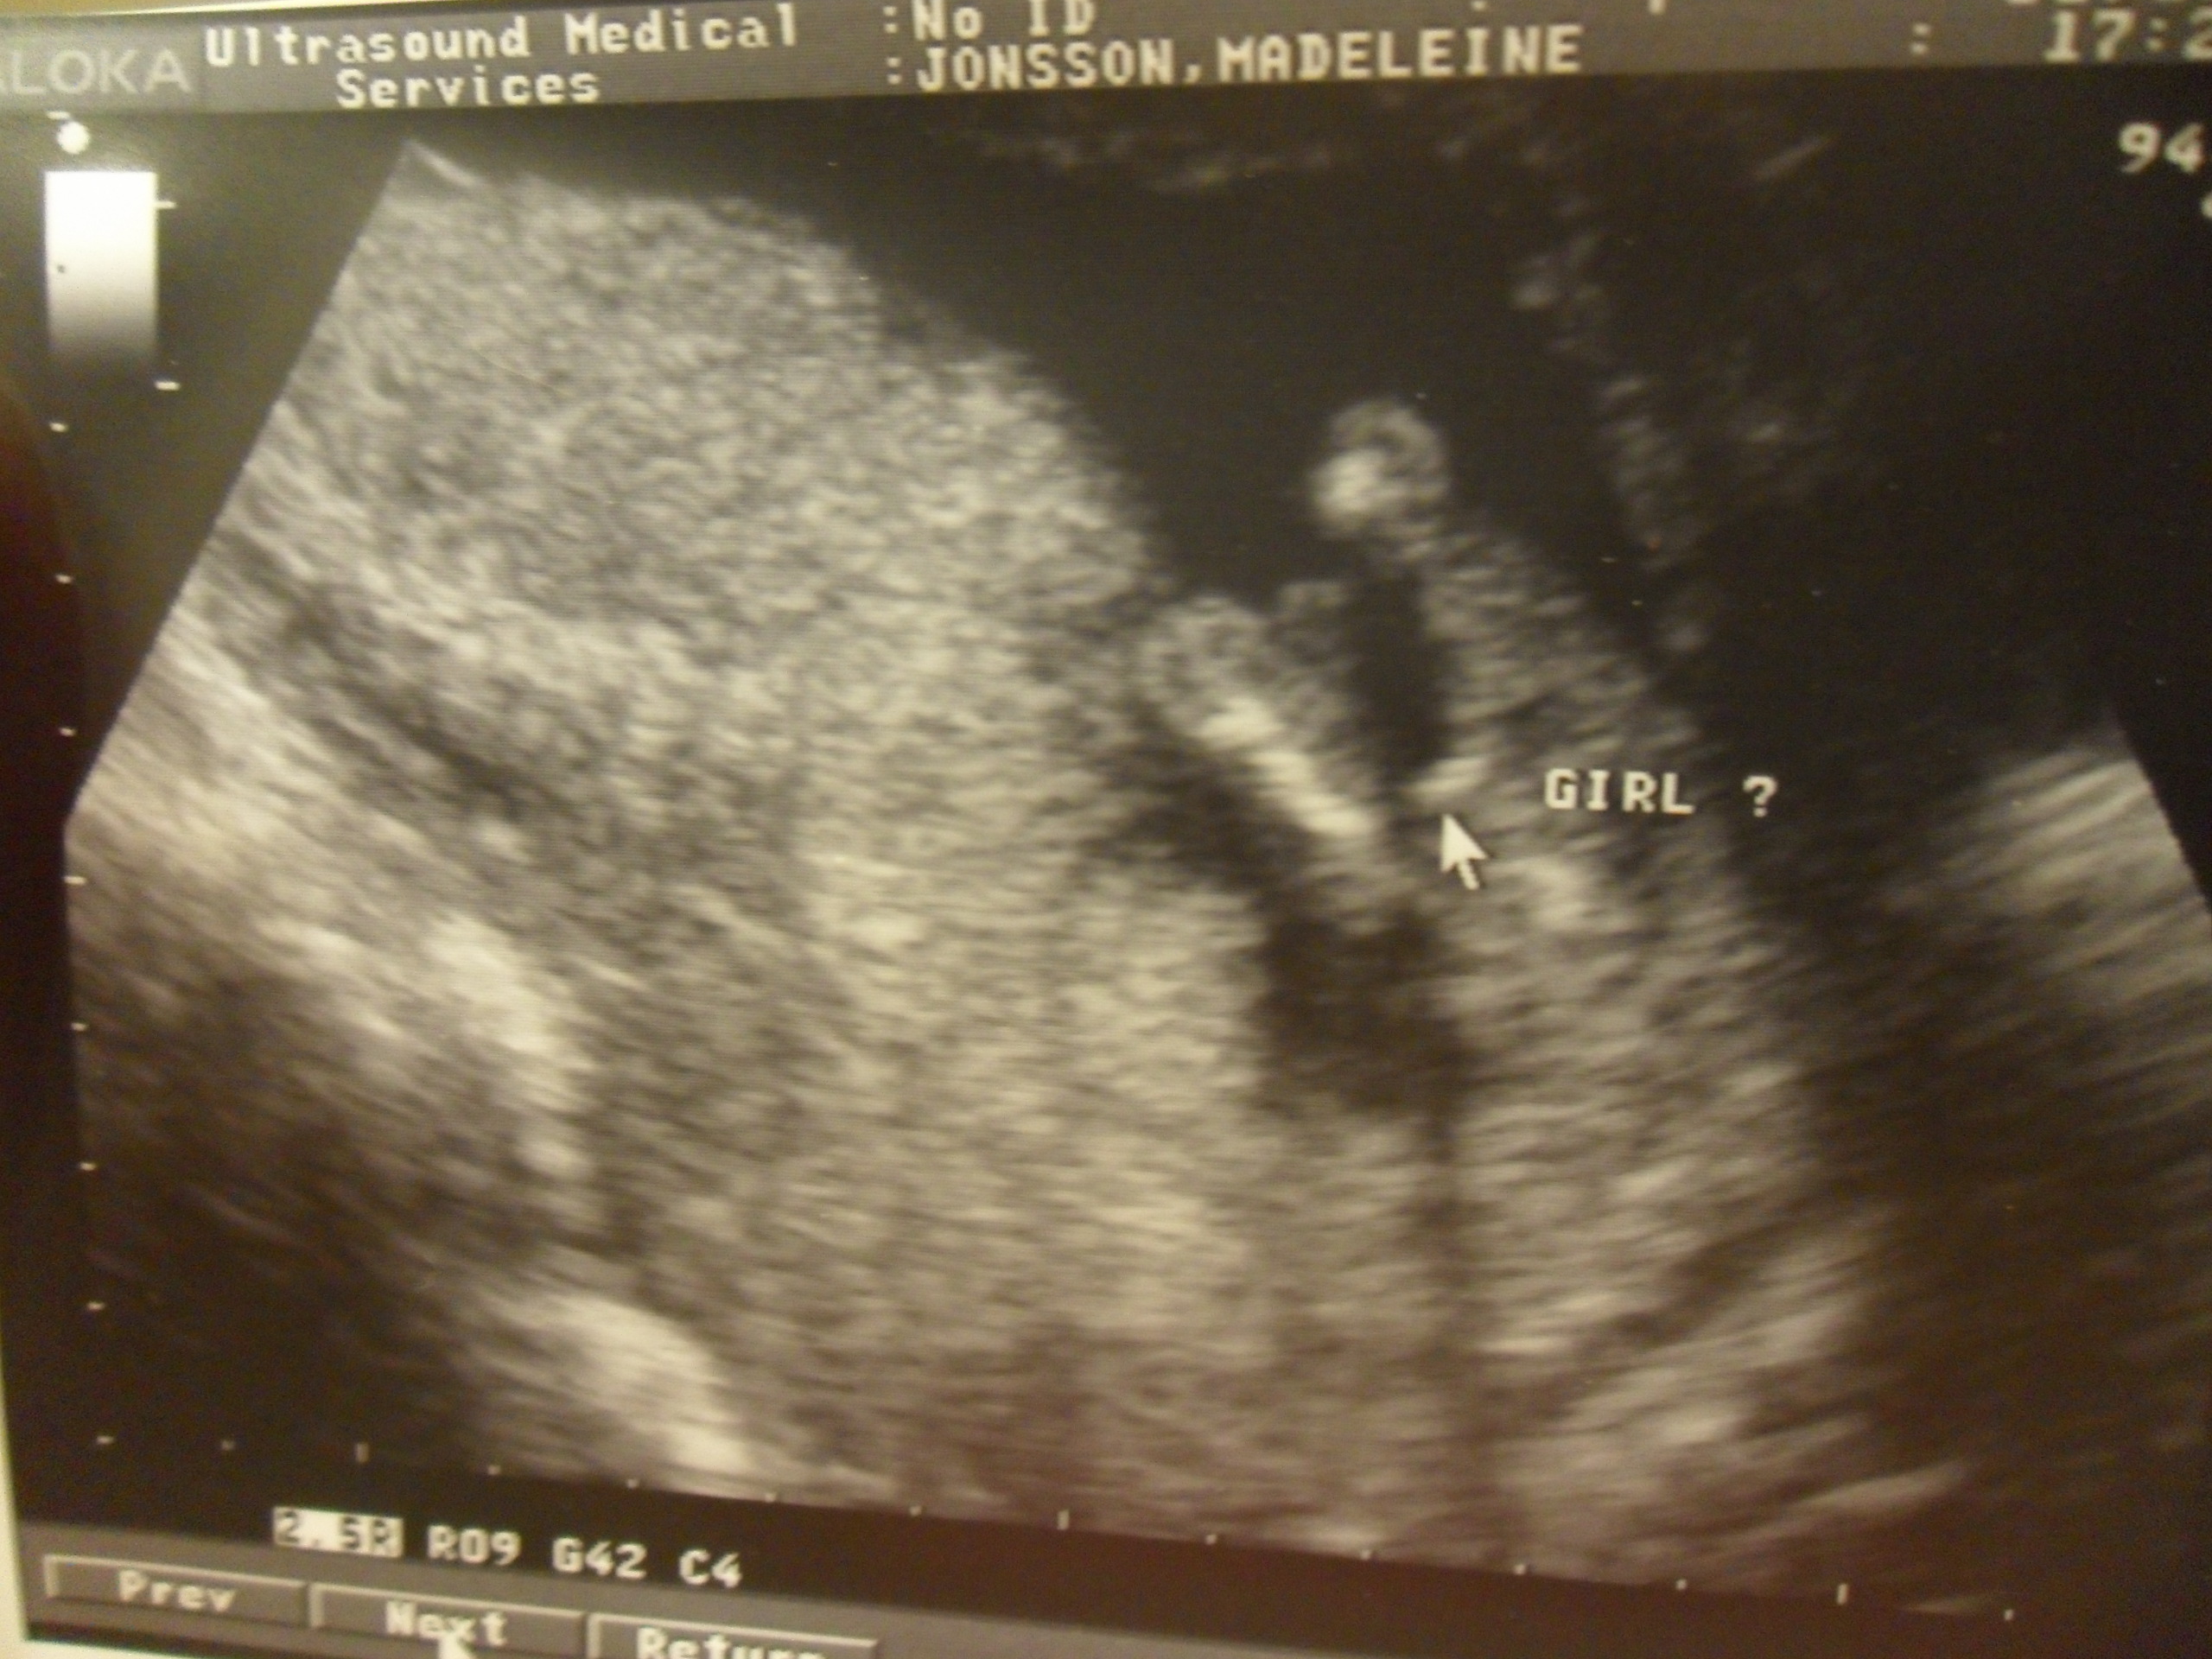

Magen växte och vi fick veta att det va en liten tjej

(en liten Mackenzie!) som jäste där inne.